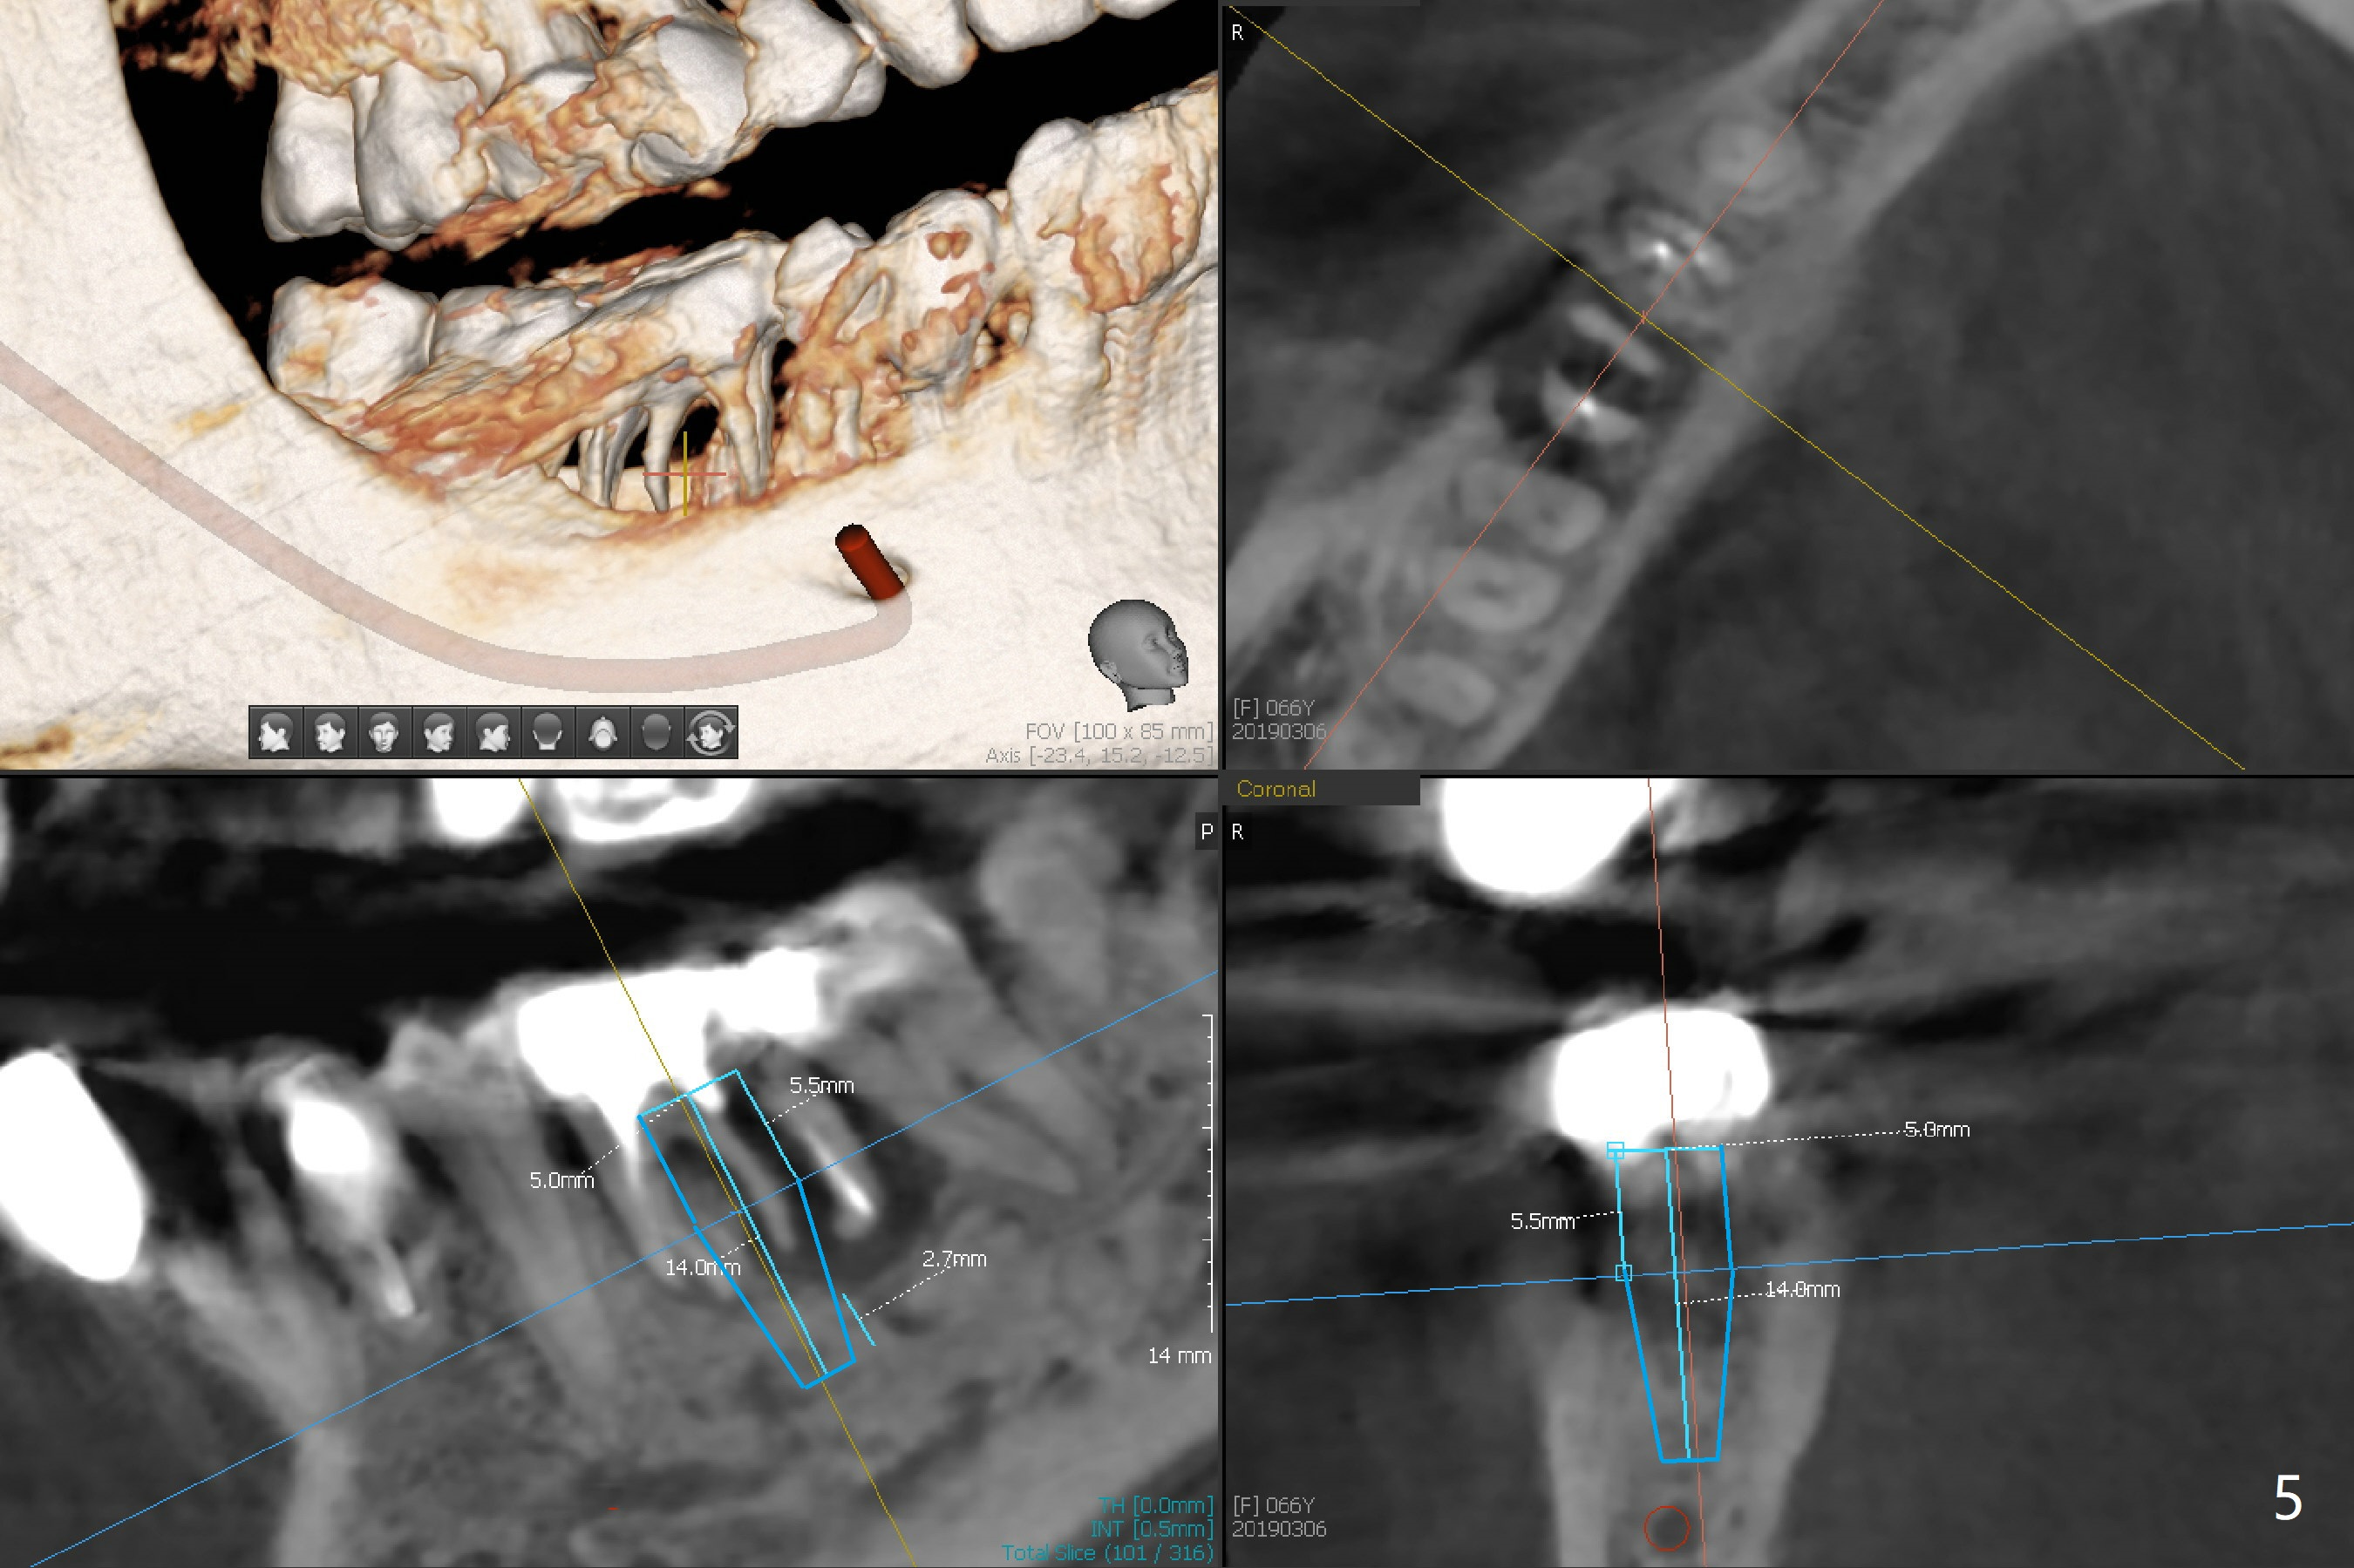

A 66-year-old woman loses a lot of bone at #30 in 4-5 months (Fig.1,2). There is severe buccal swelling, suggesting loss of the buccal plate and easy collapse of the gingiva after bone graft. In addition to an immediate provisional, periodontal dressing will be applied for support and seal. To prevent abutment screw loosening, guide will be used for implant placement in the most ideal trajectory (Fig.4). A tissue-level implant will provide with more security in prevention of screw loosening (Fig.5). If immediate implant is impossible, bone graft will be placed. Four months later, retake 5x5 cm CT for lab to determine the fitness of the guide.